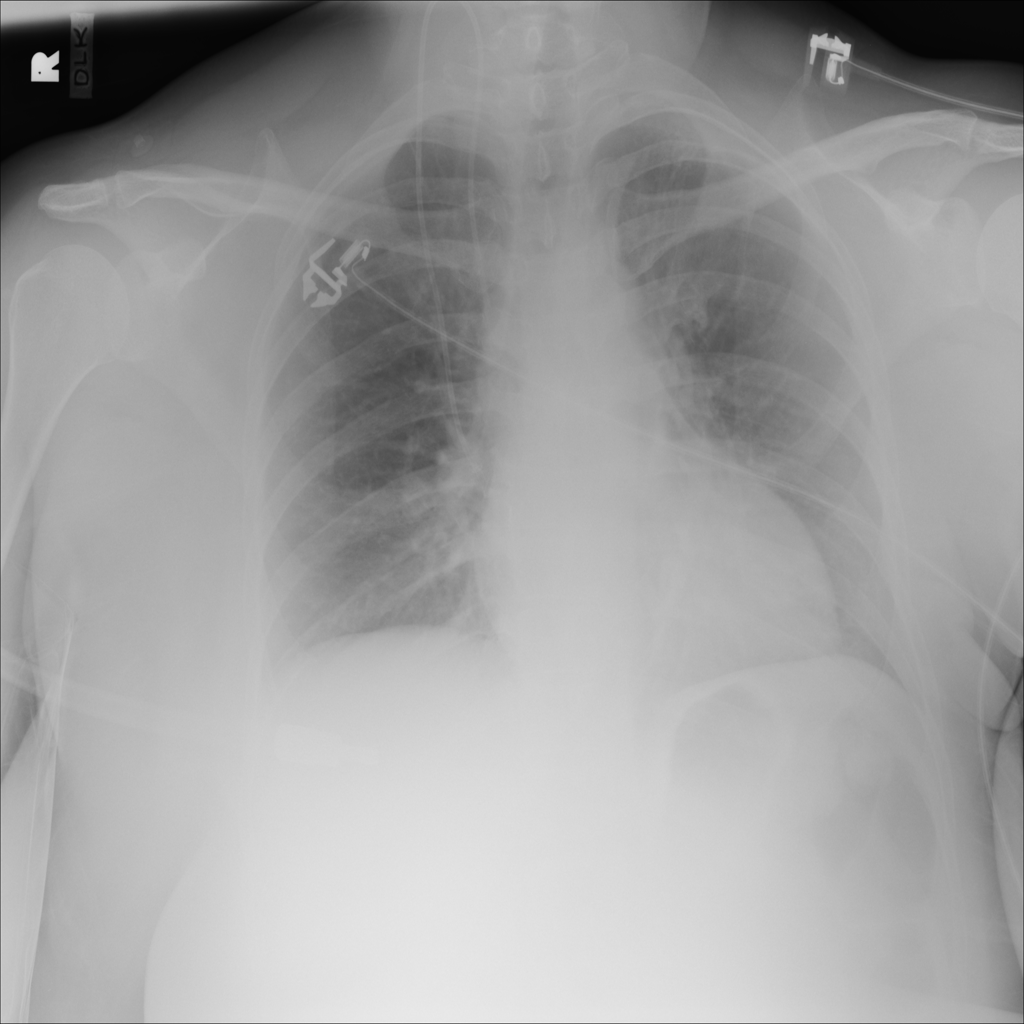

PAT-C77C · IMG-003Fibrosis

PAT-C77C · IMG-003

PA